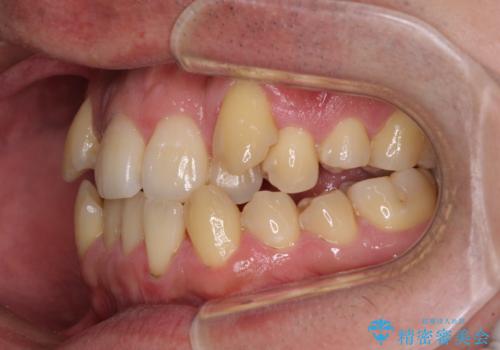

八重歯とクロスバイト 目立たないワイヤー装置で矯正治療

- 八重歯と前歯のクロスバイトを改善したいとのことで来院された患者様です。

デコボコの程度は強かったのですが、口元の突出感はなかったため、非抜歯矯正としました。

クロスバイトは、治療の過程で咬み合わせが大きく変化する期間があり、食事が取りにくくなってしまいます。

また、装置が対合歯と咬み合ってしまい、頻繁に脱落するなど、色々と面倒なことがあり、治療がスムーズに進まないことがあります。